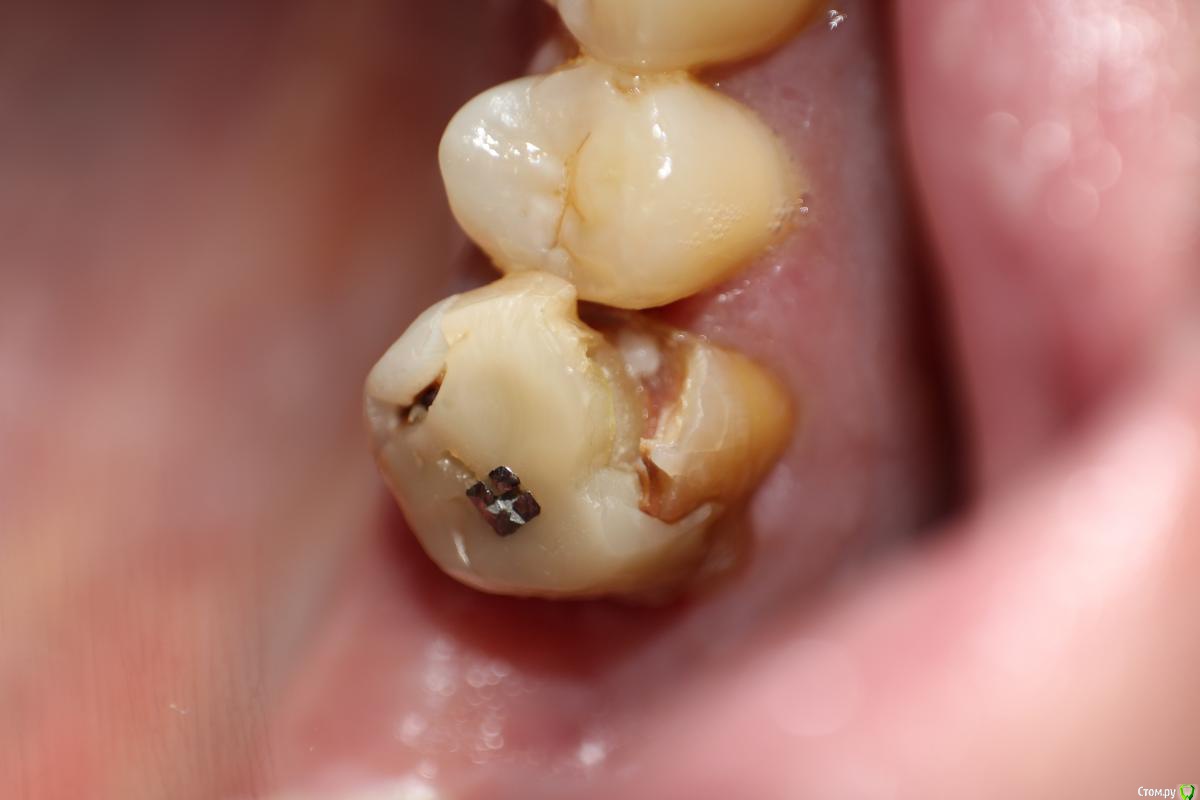

RuStom Опубликовано 8 июня, 2016 Автор Поделиться Опубликовано 8 июня, 2016 (изменено) Вот опять случай. Пришел пациент от терапевта. Зуб надо спасать. Снял пломбу, при снятии зацепил десну, все кровит. коффер даже не пытался наложить в данном случае.Имеем такую картину. На фото не совсем понятно, не чувствуется объема. Но над краем зуба миллиметра 1,5 стеночка из десны. Само "ложе для вкладки" сейчас имеет чашеобразную форму. Т.е стенки кверху становятся тоньше.Темное на фото - это я прикладывал Вискостат. Т.е чтобы сделать надежную конструкцию - мне нужно иссечь десну на уровень с корнем (а то и глубже, т.к на нынешнем уровне стенки тонкие), плюс заглубиться милиметра на 1,5, чтобы создать уступ и феррул. При этом "десна уйдет" и у 5 зуба. Как надежнее сделать? http://s33.postimg.org/8lu64zcfj/DSC_9233.jpg Изменено 8 июня, 2016 пользователем RuStom Ссылка на комментарий

krokomot Опубликовано 8 июня, 2016 Поделиться Опубликовано 8 июня, 2016 Убирайте десну, кость если нужно (если экструзии не будет), ниже края нормальных тканей зуба на 1.5-2 мм,не забудте убрать ткани ветибулярно и орально чтоб впоследствии можно было адекватно кламер одеть, плюс коепак чтоб отжать ткани, отправляем заживать, потом билдапп. Ссылка на комментарий

Паращук Роман Опубликовано 10 июня, 2016 Поделиться Опубликовано 10 июня, 2016 Канал помыть,в него Са,выравнять стенки,если жилец,то водный дентин с давлением на десну. Через сутки снимаем и оцениваем,десна должна отойти и будет виден кант зуба. Далее вкв и коронку с гирляндой. 1 Ссылка на комментарий

johniola Опубликовано 10 июня, 2016 Поделиться Опубликовано 10 июня, 2016 зуб судя по всему спасаемый.хир удлинение вкладка коронка Ссылка на комментарий